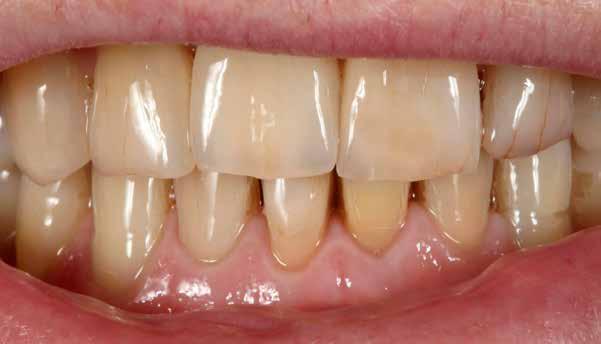

A CAD/CAM elterjedése ellenére az analóg eljárások nem szűntek meg funkcionálni. Esetbemutatásunk demonstrálja, hogyan rehabilitáltunk sikeresen az esztétikus zónában jól bevált munkamenettel, de új préskerámia recepttel. Az eredmény: természetes transzlucencia, opaleszcencia, fluoreszcencia – és egy boldog páciens.

A kiindulási helyzet recessziókkal és szabálytalan éli lefutással.

A pácienseset

Ötvenéves hölgy elégedetlen volt felső frontfogai esztétikai megjelenésével. Ezért elment a rendelőbe. Klinikailag vesztibulárisan két nagy kompozittömés volt megfigyelhető, széli elszíneződéssel. Az élek lefutása egyenetlen, aszimmetrikus volt. A frontfogakon recessziók és a nyakak szabaddá válása volt megfigyelhető. A hölgy a fogív gyors restauratív nivellálását kívánta. A nagymetszők közötti diasztémát csökkenteni kellett, de nem zárni, hogy megmaradhasson az optimális hossz-szélesség arány. A recessziók kötőszöveti fedését műtéttel kizárta. Viaszmintázat és intraorális mock-up segítségével szimuláltuk a teljes kerámiahéjakat, illetve segítettük a minimálinvazív preparációt a zománc területén. A páciens világos színű restaurációt akart. Vázanyagként a felső frontok területén a VITA AMBRIA anyagot terveztük használni, hogy a héjak életteli, színhelyes alapot kapjanak, egyidejűleg elérve az igen magas, 500 MPa-os szilárdságot. Az egyéniesítés megvalósítását VITA LUMEX AC leucit-erősítésű üvegkerámiával terveztük, hogy kevés, szín- és formastabil égetéssel reprodukálhassuk a fogakat. A 23-as szemfogat – palatinálisan megfigyelhető defektusa miatt – egyedüliként teljes koronával terveztük rehabilitálni, ugyanezzel az anyagkombinációval. A bukkális folyosó feltöltése érdekében a premolárisokra is héjak kerültek. Ezek természetes fluoreszcenciájának, transzlucenciájának és opaleszcenciájának eléréséhez monolit VITA AMBRIA munkákat készítettünk, felszíni festéssel.